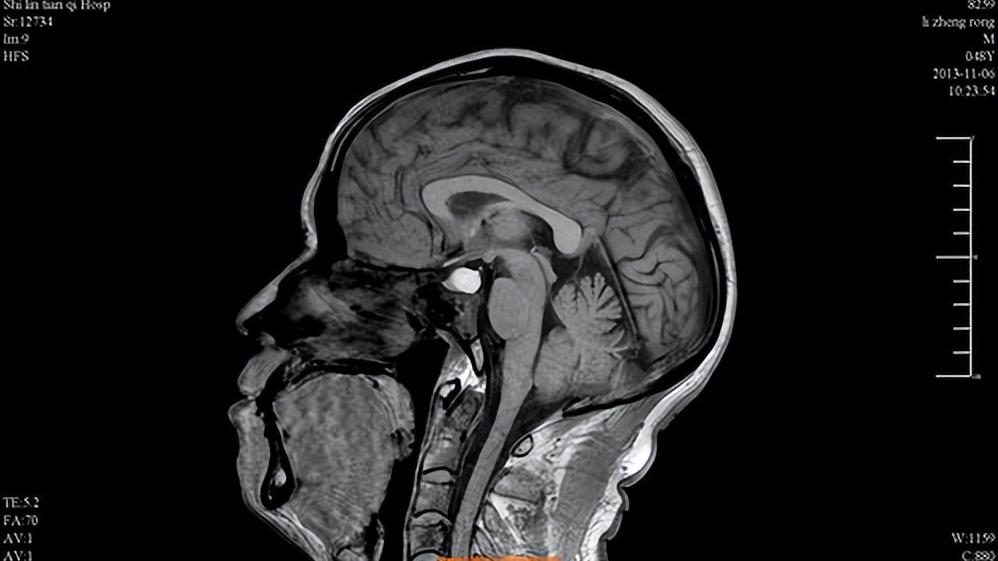

此外,垂体肿瘤也会导致垂体性闭经。这是因为垂体生长激素瘤会压迫门脉系统,导致其他正常的垂体组织受压,长时间致使萎缩。腺垂体分泌的雌激素和孕激素相应减少,从而出现闭经的情况。

还有就是脑脊液流入蝶鞍的垂体窝,使蝶鞍扩大,持续压迫垂体。这时垂体不断受压缩小,也会导致闭经。而脑脊液外溢的因素很多,比如脑癌放疗、空蝶鞍综合征、腰椎穿刺刺破蛛网膜等。出现这种情况应尽早前往医院治疗,避免垂体功能长时间受影响导致不可逆的损伤。